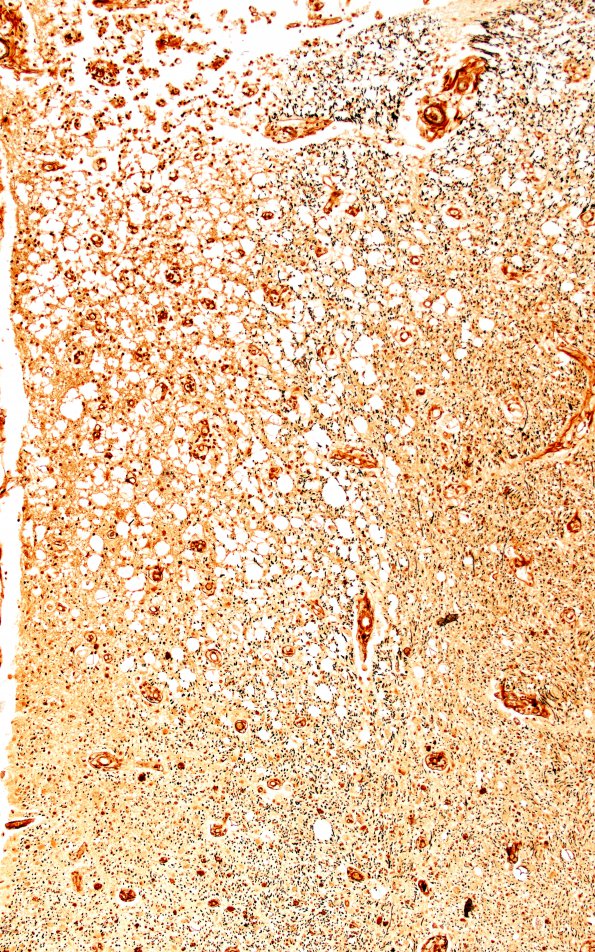

The area of 1G1 marked with an arrow is shown stained for axons (Bielschowsky). In this series both axons and myelin are lost comparably